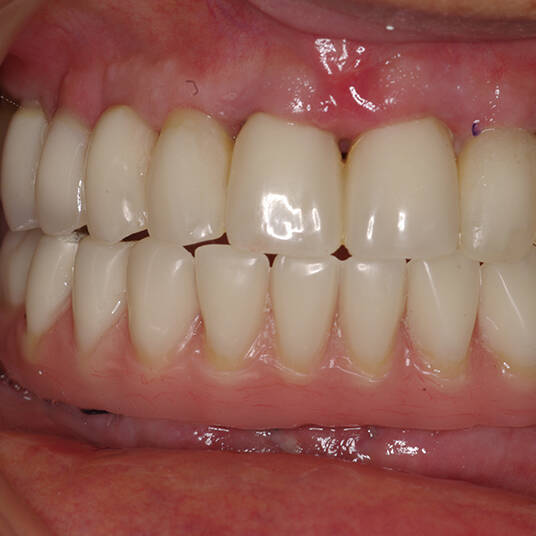

A Carga Imediata é uma técnica odontológica avançada que permite a colocação de uma prótese dentária fixa logo após a cirurgia de instalação dos implantes ou em poucos dias. Isso elimina a espera tradicional de meses para a integração completa do implante ao osso, oferecendo uma solução rápida e segura para restaurar dentes perdidos.

- Fixação da Prótese: Em até 72 horas após a cirurgia, a prótese provisória é instalada, permitindo que o paciente recupere a funcionalidade e a estética imediatamente.

- Recuperação rápida: O paciente sai do consultório com um sorriso renovado em questão de dias.

- Conforto e Estética: A prótese provisória é funcional e visualmente semelhante aos dentes naturais.